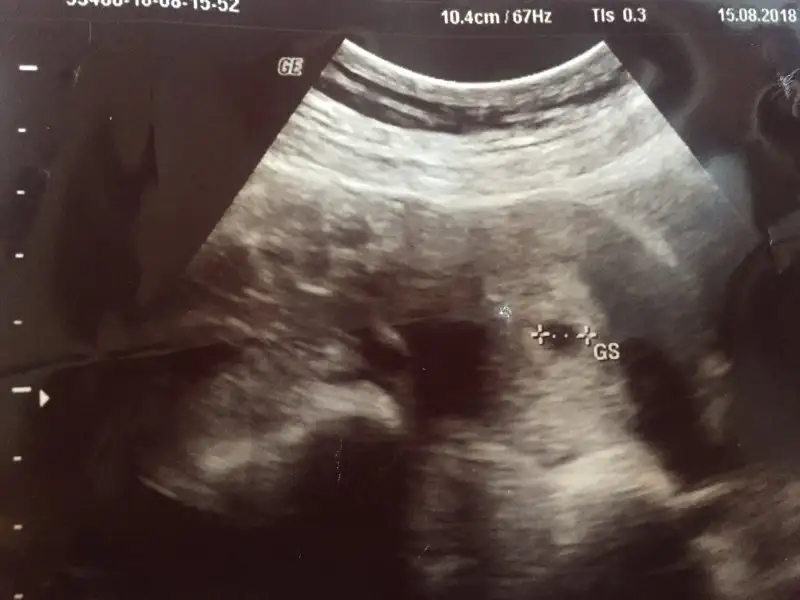

Aksine koyu olmasi iyiymis bekleyen kan olduguna isaretmis. Acik olmasi sorunmus. Benim bir ara aciga dondu. Cok feci urktum. Bir de henuz kese falan olmadigi icin doktor da bir sey yapamiyor. Ilacla desteklemeyi de dogru bulmuyor henuz cok kucuk oldugu icin. Olumlu dusunmek lazim. Kuzularimiz bizden cok etkileniyor. Ben de cok agladim gordugumde falan ama sonra dua ettim bolca ona inandigimi soyledim.. biraz koruyacagiz artik. Gerisi Allah in takdiri.. hayirlisi olsun hakkimizda insallah.Benim de dünya kadar işim var ama aynı şekilde yattığım yerden kalkmıyorum neredeyse. Kaç gündür kahverengi olarak geliyordu da rengi koyulaşınca korktuminşallah sıkıntı olmaz canım sağlıkla zamanında alırız kucağımıza, şu an başka hiçbir şey düşünemiyorum.

Ben tam tersi olarak biliyordum koyu olunca riskli şeklinde yanlış biliyormuşumAksine koyu olmasi iyiymis bekleyen kan olduguna isaretmis. Acik olmasi sorunmus. Benim bir ara aciga dondu. Cok feci urktum. Bir de henuz kese falan olmadigi icin doktor da bir sey yapamiyor. Ilacla desteklemeyi de dogru bulmuyor henuz cok kucuk oldugu icin. Olumlu dusunmek lazim. Kuzularimiz bizden cok etkileniyor. Ben de cok agladim gordugumde falan ama sonra dua ettim bolca ona inandigimi soyledim.. biraz koruyacagiz artik. Gerisi Allah in takdiri.. hayirlisi olsun hakkimizda insallah.

Ben de dün keseyi gördümÇok şükür

Sizi o kadar iyi anliyorum kii.. inanin her dakika leke gelmis mi diye bakiyorum. Akinti hisseder gibi oluyorum hemen lavobaya gidiyorum.. korkutucu bir surec. Keseydi kalp atisiydi bir duysak gorsekte birazcik olsun rahatlsakBen tam tersi olarak biliyordum koyu olunca riskli şeklinde yanlış biliyormuşumilaç olayını ben de duydum evet belli bir süre vermiyorlarmış kanamalarda. Ben de gördüğümden beri ağlıyorum biliyorum stres yapmamamız gerekiyor ama elimde değil bir de göğüs ağrım falan hafifliyor ara ara her şeyi takip eder oldum şu an hepsi endişelendiriyor. Doktora gidene kadar içim rahat etmeyecek. Hayırlısı tabi umarım sorunsuz geçer bu süreçlerimiz.

Ben de aynısını diyorum keseyi görsek kalp atışını duysak da bi rahatlasak,kendimizi de bebeklerimizi de daha fazla strese sokmasak artıkSizi o kadar iyi anliyorum kii.. inanin her dakika leke gelmis mi diye bakiyorum. Akinti hisseder gibi oluyorum hemen lavobaya gidiyorum.. korkutucu bir surec. Keseydi kalp atisiydi bir duysak gorsekte birazcik olsun rahatlsak